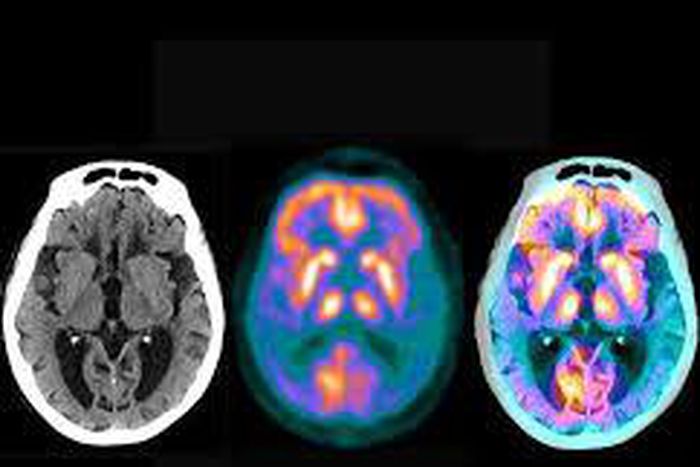

The study, published Monday in JAMA, is the first large, randomized clinical trial to find something that can help many older people reduce their risk of mild cognitive impairment — an early stage of faltering function and memory that is a frequent precursor to Alzheimer’s disease and other dementias.